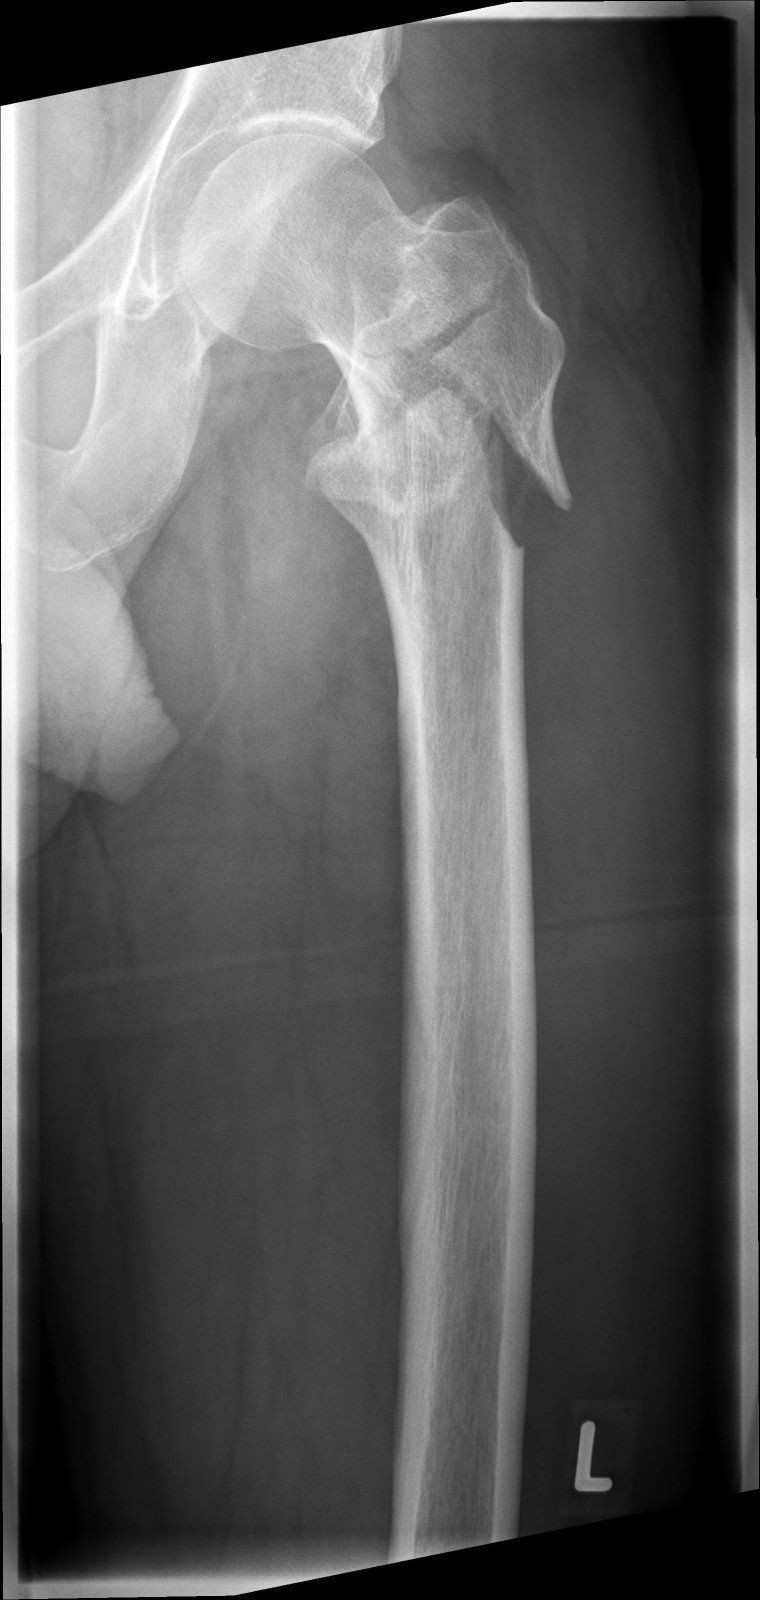

Titan ist es, darf im Körper bleiben.Puh, sieht ja heftig aus. Was verbauen die denn da so? Titan?

Zumindest mal der halbe Oberschenkel. Der Nagel ist 20cm lang, die Schraube oben 13cm. Ist schon massiv. Wie sagte ich vorhin zu meinen besten Freund: Nach meinen Tod lohnt sich das ausschlachten!Ach du meine Güte, hast du vor, langsam eine Maschine zu werden? Das halbe Bein besteht als Metall.

Zumindest mal der halbe Oberschenkel. Der Nagel ist 20cm lang, die Schraube oben 13cm. Ist schon massiv. Wie sagte ich vorhin zu meinen besten Freund: Nach meinen Tod lohnt sich das ausschlachten!

Übrigens verlagere ich gerade mehr und mehr Gewicht nahezu ohne Schmerzmittel auf das linke Bein. Mein persönliches Ziel ist zu Weihnachten mit einer Gehstütze unterwegs zu sein. Reha ist natürlich erst im Januar.